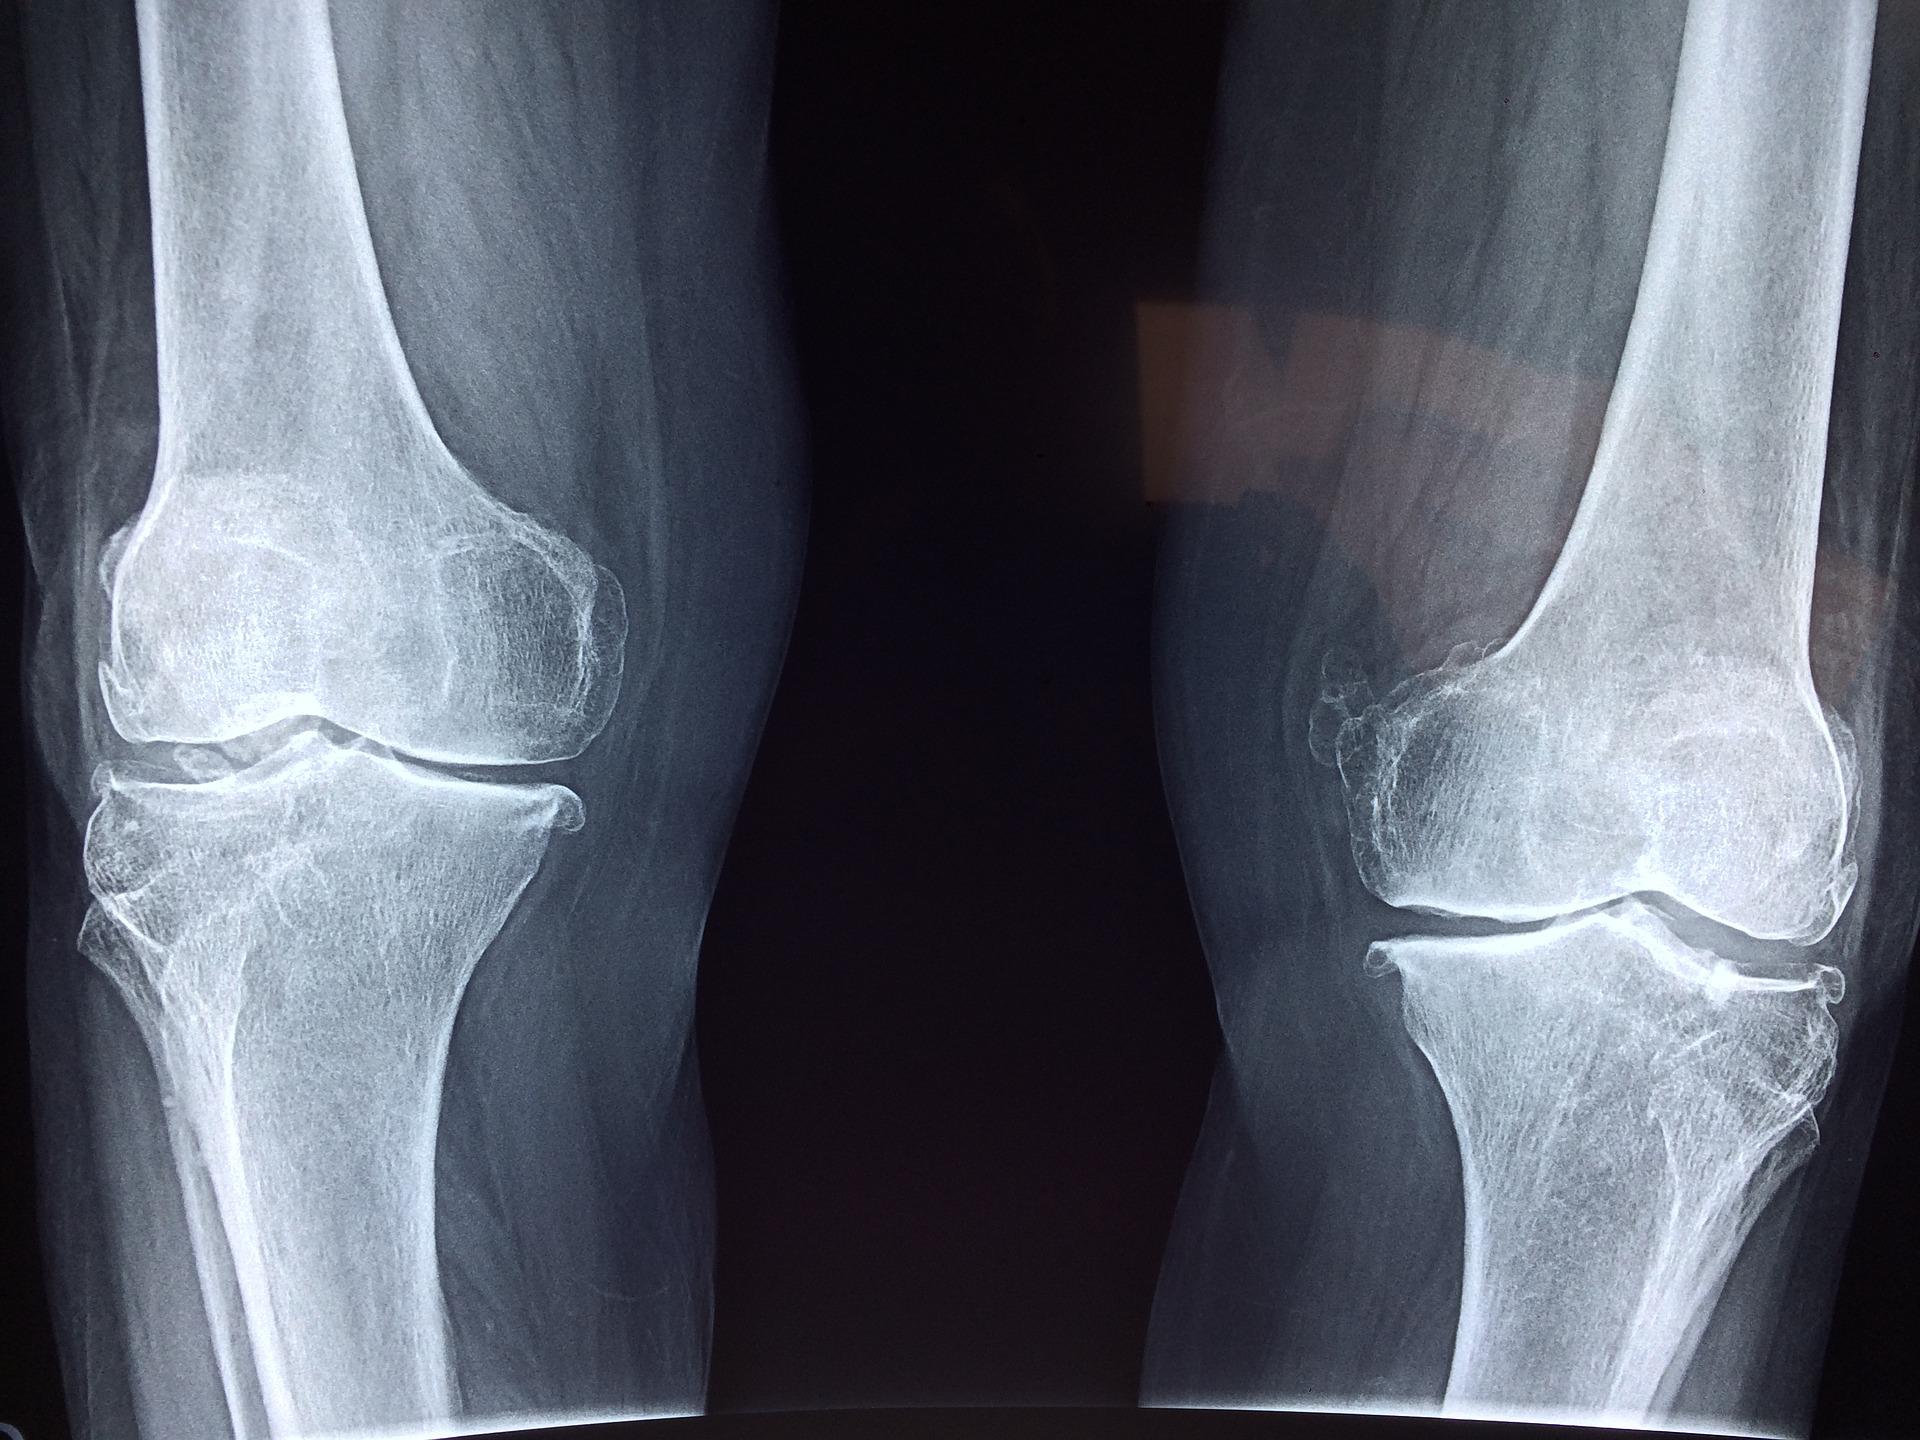

Tissue Injury

Sometimes severe slip and fall Accidents cause tissue strains. For instance, the ligaments in knee injuries that can be resulted from slip and fall accidents need to be rehabilitated or even surgery, which prevents the victim from working during his recovery. In these cases, the victim can file a slip and fall case against the liable person with the help of an attorney to seek compensation for the victim's medical attention and replacement for his future earnings.